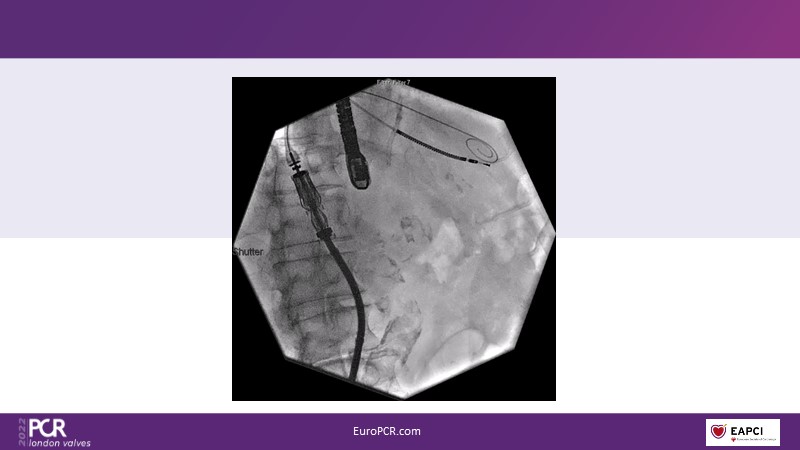

The right valves for the right ventricle: Venus MedTech tricuspid and pulmonary replacement systems

In this session from PCR London Valves 2022, discover the new Venus MedTech technology for tricuspid and pulmonary valve replacement, and a review of the clinical indications, selection criteria and procedural details.

- To learn about Venus MedTech technology, clinical indications and procedural details of valve replacement systems

- To learn more about the clinical experience and outcomes with Cardiovalve tricuspid and Venus P-valve